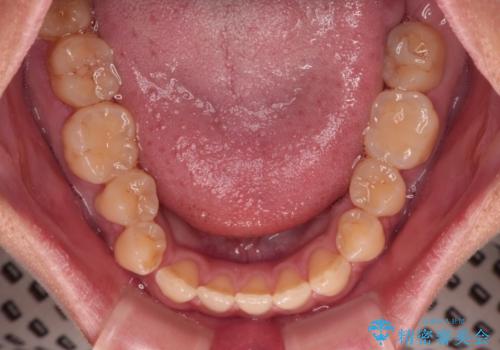

- 極端な開咬を気にして来院された患者様です。

開咬の方の特徴として、幼少期の指しゃぶりの癖や、強い舌の突出癖が挙げられます。

こちらの患者様も強い舌の突出癖が認められたため、矯正治療を行うにあたり、舌のトレーニングをしっかりと行っていただくように指示をいたしました。

開咬はインビザラインが得意とする歯列不正であるため、舌のトレーニングを行いながら、インビザラインにて矯正治療を行うこととしました。

担当医としては、もっと上下の前歯を接触させるところまで治療を進めたいという思いがありますが、今まで咀嚼できなかったものが食べられるようになったということで、この状態で治療終了となりました。